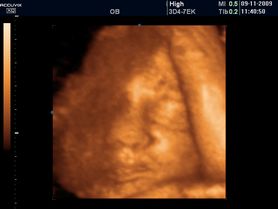

Zdjęcia płodu - twarze